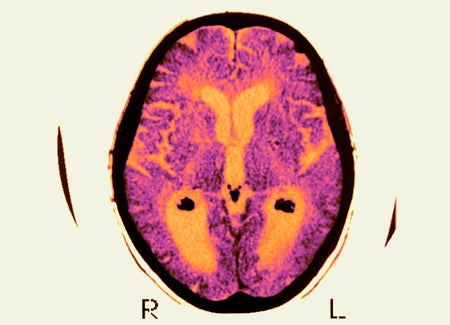

A new study finds that dementia cases will increase at a much higher rate than expected, with lifetime risk rising to 42 percent after age 55